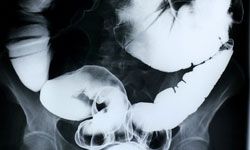

Gastric Cancer